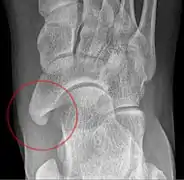

The Geist classification divides the accessory navicular bones into three types.[3]

• Type 1: An os tibiale externum is a 2–3 mm sesamoid bone in the distal posterior tibialis tendon. Usually asymptomatic.

• Type 2: Triangular or heart-shaped ossicle measuring up to 12 mm, which represents a secondary ossification center connected to the navicular tuberosity by a 1–2 mm layer of fibrocartilage or hyaline cartilage. Portions of the posterior tibialis tendon sometimes insert onto the accessory ossicle, which can cause dysfunction, and therefore, symptoms.

• Type 3: A cornuate navicular bone represents an enlarged navicular tuberosity, which may represent a fused Type 2 accessory bone. Occasionally symptomatic due to bunion formation.